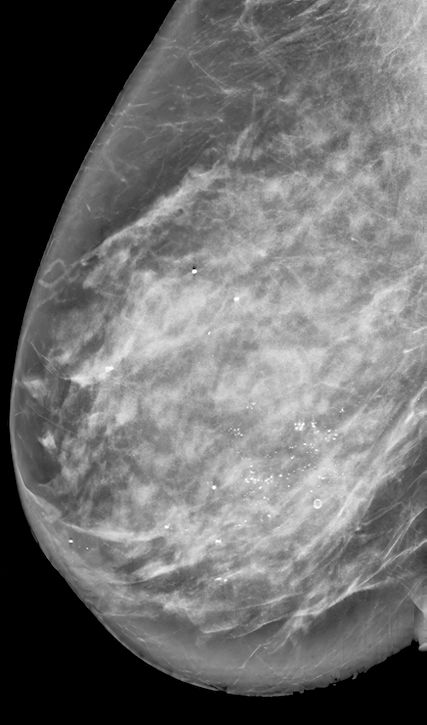

Das duktale Carcinoma in situ (DCIS) beschreibt eine Vorstufe des Mammakarzinoms, bei der maligne Zellen innerhalb der Milchgänge wachsen, jedoch die Basalmembran noch nicht durchbrochen haben (Abb.1). DCIS gilt als nicht zwingender, aber möglicher Vorläufer eines invasiven Karzinoms.1 Daher bestand die Standardtherapie bisher meist aus operativer Entfernung, adjuvanter Radiotherapie und – bei Hormonrezeptorpositivität – endokriner Therapie, in Analogie zum invasiven Mammakarzinom. Mit verbesserter Bildgebung wie Tomosynthese-Mammografie, Früherkennungsprogrammen und zunehmender Durchführung von Magnet- Resonanz-Imaging (MRI) werden heute vermehrt kleine, niedriggradige DCIS-Läsionen entdeckt.2 Studien zeigen jedoch, dass nicht jedes DCIS fortschreitet, und bei operativer Entfernung findet sich nur bei etwa 10–23% ein invasives Karzinom.3 Zudem führte der Anstieg an DCIS-Diagnosen nicht zu einem signifikanten Rückgang der Zahl an invasiven Karzinomen oder der Brustkrebssterblichkeit. Dies wirft die Frage nach einer möglichen Übertherapie auf.4

Abb. 1: DCIS, H&E-Färbung. Bild mit freundlicher Genehmigung von Prof. Varga